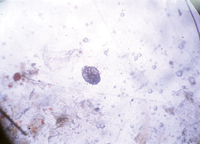

Foto 1: Huevos de Sarcoptes scabiei en un raspado de piel.

La sarna canina, producida por Sarcoptes scabiei variedad canis, es una infestación transmisible de la piel de los perros que se puede transferir a otras especies. El ácaro de la sarna tiene un ciclo biológico de 17 a 21 días, la hembra excava una madriguera en la piel y pone sus huevos tras ella (Foto 1).

El raspado de la piel puede producir ácaros, restos fecales o huevos (tener en mente que el raspado puede ser negativo hasta 70% de las veces).